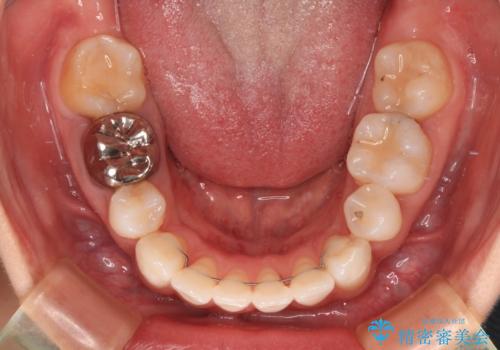

4本の歯を抜歯したことで、飛び出していた口元が引っ込み、横顔が大きく改善されました。